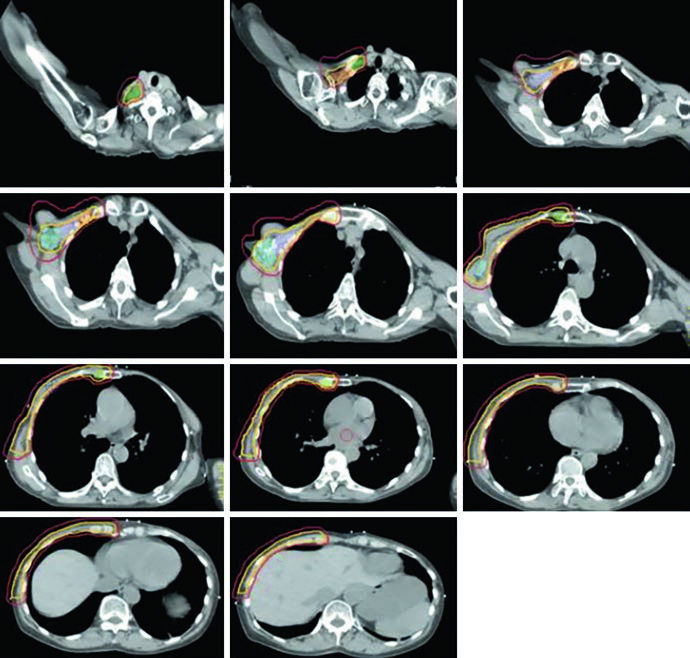

Unreconstructed Right Chest Wall

In the post-mastectomy setting without reconstruction, the chest wall constitutes the primary CTV alongside the nodal volumes. Figures 12.1 and 12.2 (coronal and sagittal) and Figure 12.3 (axial slices) illustrate how the contours are distributed: the PTV follows the curvature of the remaining chest wall, with nodal stations contoured contiguously.

Without a prosthesis or expander in the field, planning is more straightforward. The chest wall is relatively flat, allowing tangents with conventional angulation. The main challenge lies in ensuring uniform skin coverage and adequate retrosternal coverage where the IMN reside, without excessive ipsilateral lung dose. The absence of prosthetic volume reduces dosimetric complexity but does not eliminate the need for optimization — especially at the junction between tangential and supraclavicular fields.